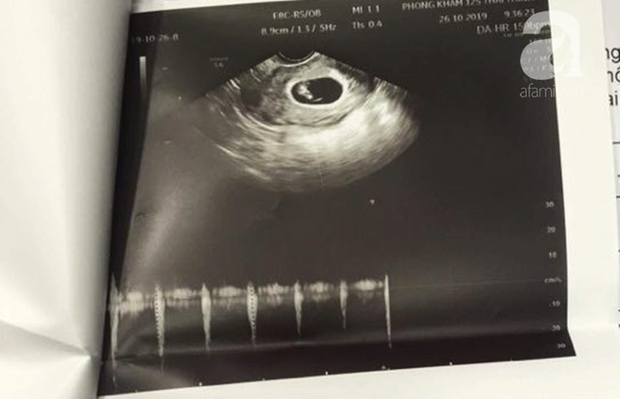

Phiếu siêu âm của bệnh nhân tại một bệnh viện ở Hà Nội.